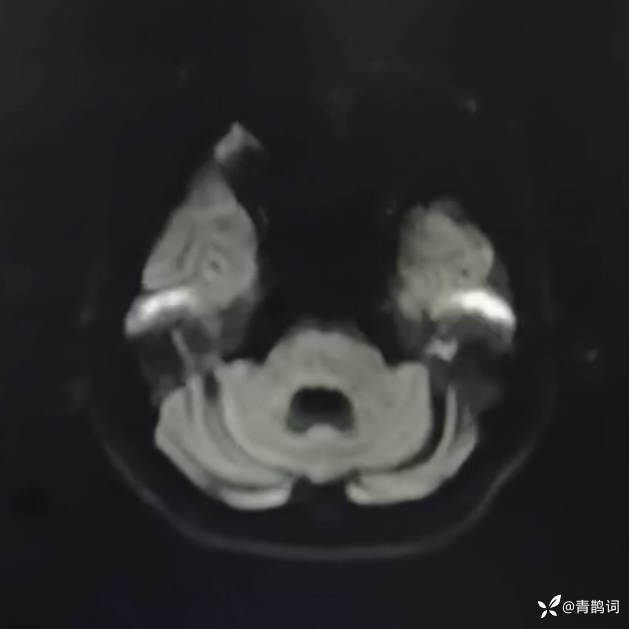

乐痴于医等 2人推荐简要病史:42岁男性,记忆力下降及听力下降一年余。既往体健,否认前驱感染病史。否认家族史。三个月前就诊于当地医院,自述腰穿脑脊液乳酸增高。现就诊于我院,查体记忆力下降,计算力下降,定时定向差,吟诗样语言。完善磁共振如下:

FLAIR: